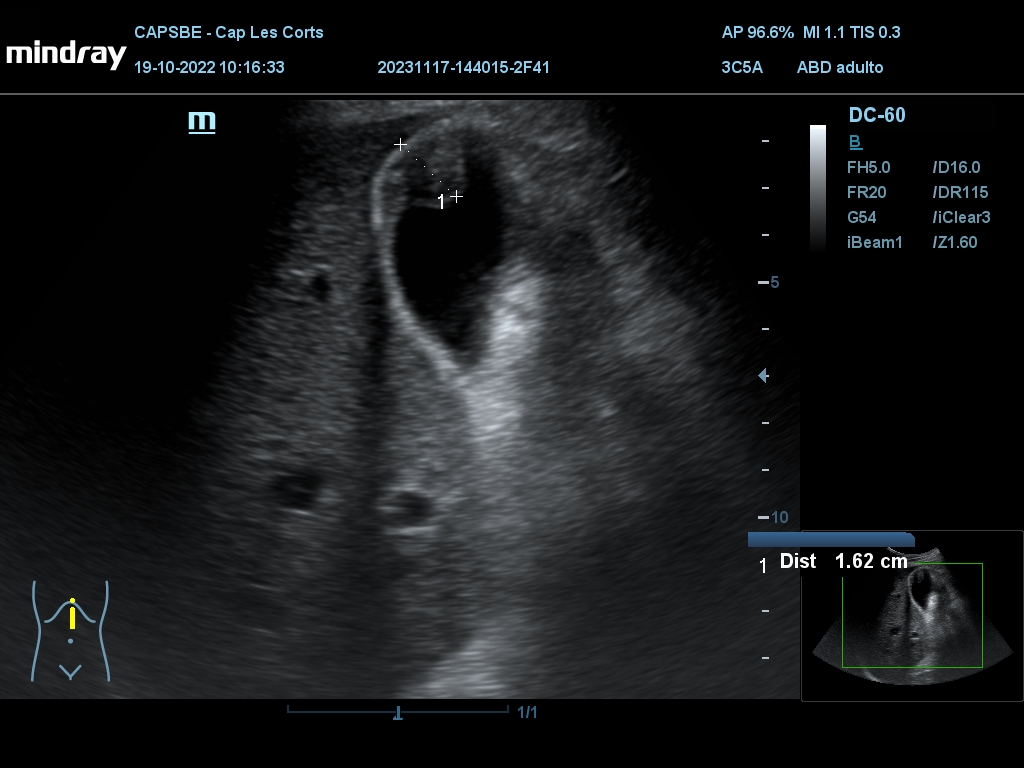

Hallazgos ecográficos

Derrame pericárdico. Vesícula biliar con grosor parietal de 1,6 cm, heterogénea, no se moviliza con cambios posturales. Quistes renales derechos, mayor de 7 cm. Aorta ateromatosa y aneurismática de 36 x 42 mm. Sin líquido intraabdominal.

(Se adjuntan imágenes del derrame, engrosamiento biliar, riñón derecho y aneurisma de aorta).